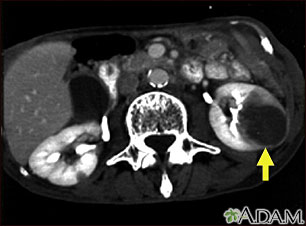

A CT scan of the middle abdomen showing metastasis (cancer that has spread) in the left kidney in a patient with carcinoma of the lung. Note the large dark circular tumor in the kidney on the right side of the picture.